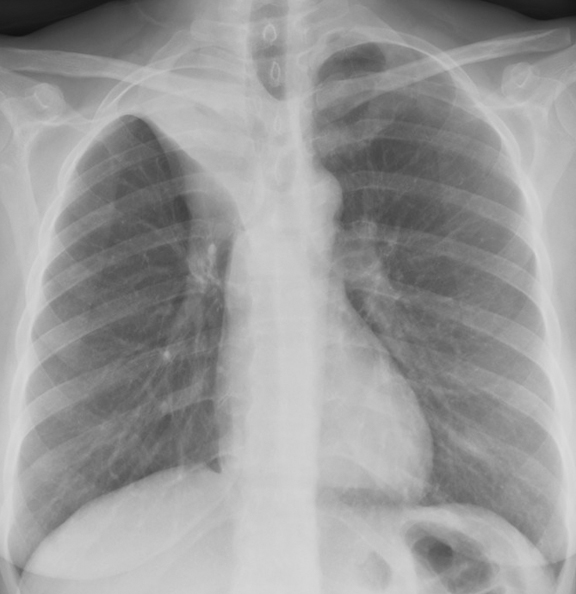

Lobar Collapse

RUL Collapse

RUL Collapse Case 7 PA